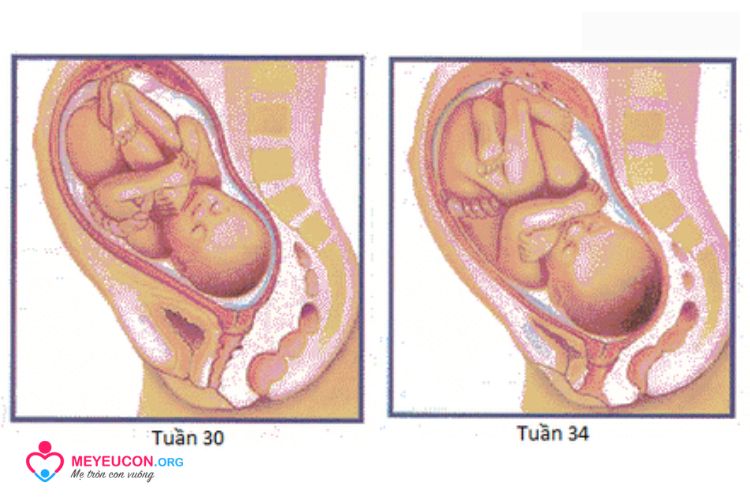

Tuần 30

Chiều dài: 28 cm, trọng lượng: hơn 1360 g

Da trẻ dày và màu hồng hơn. Có sự gia tăng trong các kết nối giữa các tế bào thần kinh trong não. Từ giai đoạn này, thai nhi phát triển các trung tâm, chủ yếu là xung quanh tăng trưởng.

Có 95% cơ hội để trẻ sống sót nếu được chăm sóc sơ sinh thích hợp.

Tuần 34

Chiều dài: 31 cm, trọng lượng: 2490 g

Tóc trên đầu mượt mà hơn và mọc dựng đứng. Trương lực cơ đã phát triển và thai nhi có thể quay hoặc ngẩng đầu của mình. Có trên 95% cơ hội sống sót cho trẻ sinh ra ở tuần này khi được chăm sóc sơ sinh thích hợp.